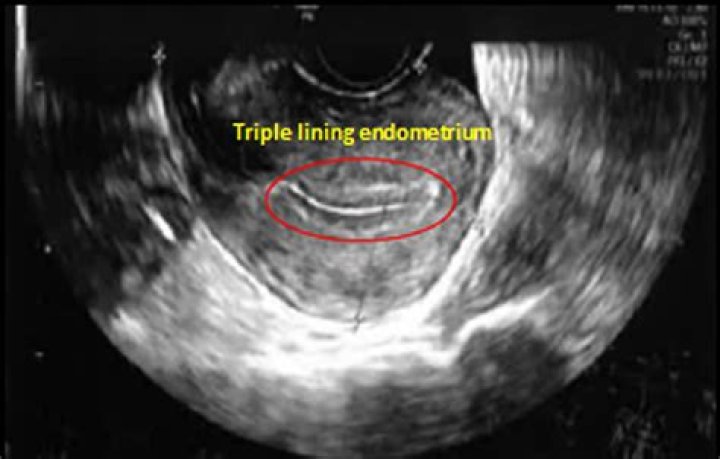

A: Every menstrual cycle and for >400 such cycles in a woman's reproductive life span, the uterus sheds its inner lining to a thickness of ~4-10 mm and is completely regenerated back within a week. The process has both evolutionary as well as physiological significance.